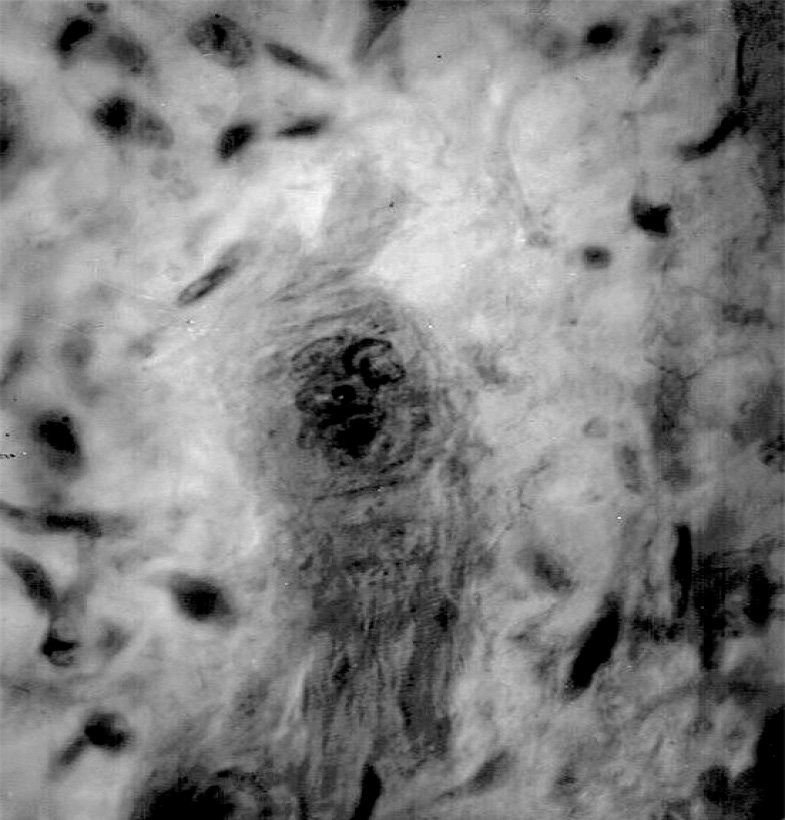

В печени после нанесения травмы сформировалась зона некроза, представленная розовой аморфной массой с примесью эритроцитов, в которой определялись гепатоциты с размытыми границами с признаками кариолизиса. Площадь повреждения составляла 3085,7±368,3 мкм2. С 1-х суток после операции в печени нарастало число митозов гепатоцитов (4,5±1,4; в контроле — 1,5±0,7). Активация митотической активности гепатоцитов подтверждалась повышенным количеством у опытных плодов Ki-67-позитивных ядер в гепатоцитах по сравнению с контрольными животными (15,3±0,7 на 7-е сутки; в контроле — 6,4±0,8) (рис. 4). Пик митозов наблюдался в сроки от 2 до 7 сут (8,0±3,5 — на 7-е сутки; в контроле — 3,6±0,7). Начиная с 7-х суток по мере снижения числа митозов увеличивалось число двуядерных гепатоцитов (38,1±5,2 — на 7-е сутки; в контроле — 25,3±4,5), что продолжалось до конца эксперимента (37,1±4,6 — на 30-е сутки; в контроле — 26,4±3,6).

Рис. 4. Позитивная реакция ядерного белка Кi-67 в ядрах гепатоцитов, 7-е сутки после операции: а — контрольное животное; b — опытное животное. Иммунногистохимическое окрашивание, ×400.

Fig. 4. Positive reaction of the nuclear protein Ki-67 in nuclears of hepatocytes, 7th day after the operation: а — control animal; b — experienced animal. Immunohistochemical staining, ×400.